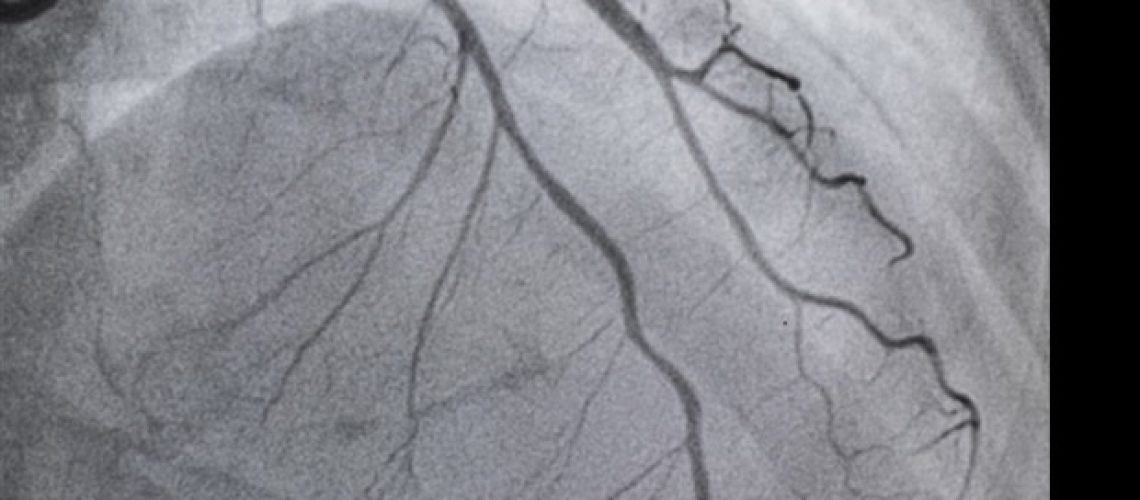

חולים עם מחלת עורקים כליליים – הצטברות רובד בתוך העורקים שמובילה לכאבים בחזה, קוצר נשימה והתקף לב – עוברים לעתים קרובות PCI, הליך לא ניתוחי שבו קרדיולוגים התערבותיים משתמשים בצנתר כדי להציב סטנטים בכלי הלב החסום עורקים לשיקום זרימת הדם. קרדיולוגים התערבותיים משתמשים לרוב באנגיוגרפיה להנחיית PCI, הכוללת צבע מיוחד (חומר ניגודי) וקרני רנטגן כדי לראות כיצד הדם זורם דרך עורקי הלב כדי להדגיש חסימות כלשהן.

עם זאת, לאנגיוגרפיה יש מגבלות, המקשות על קביעת גודל העורק האמיתי והרכב הרובד, והיא לא אופטימלית בזיהוי האם הסטנט מורחב במלואו לאחר PCI ובזיהוי מצבים אחרים המשפיעים על התוצאות המוקדמות והמאוחרות של הסטנט. תהליך. אולטרסאונד תוך וסקולרי הוצג לפני יותר מ-30 שנה כדי לספק תמונה מדויקת וספציפית יותר של העורקים הכליליים. למרות שמחקרים הראו כי PCI מונחה IVUS עדיפה על PCI מונחה אנגיוגרפיה ומפחיתה אירועים קרדיווסקולריים, הוא משמש רק בכ-15 עד 20 אחוז ממקרי ה-PCI בארצות הברית, מכיוון שהתמונות עשויות להיות קשות לפירוש ההליך אינו מוחזר במלואו.